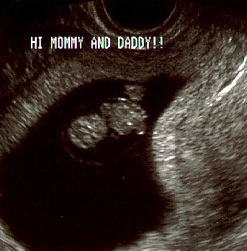

توأمان في الاسبوع الخامس

يبدأ الجنين في الأسبوع الخامس في بداية تكوينه ويسمى في هذه الفترة وحتى 3 شهور (حميل) والحميل هو الجنين منذ بداية تلقيح البويضة وحتى الأسبوع 12. فهو الآن ينمو داخل الرحم. وينقسم إلي ثلاث طبقات تكون كل طبقة منهم الأعضاء والأنسجة فيما بعد. وفي مؤخرة الرأس لأسفل، هناك طبقتين نسيج تكون الأذن بعد ذلك.